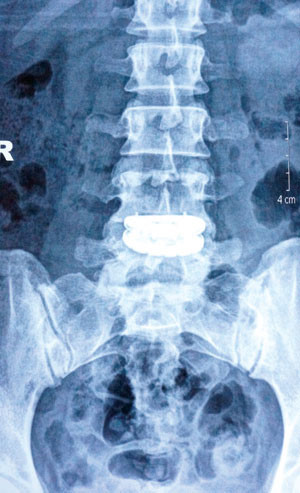

| Phim chụp vị trí thay đĩa đệm nhân tạo. |

Khi đến khám tại bệnh viện Việt Đức, chị được các bác sĩ chẩn đoán bị thoát vị đĩa đệm L4, L5 trái, phải mổ thay đĩa đệm nhân tạo cột sống thắt lưng, nếu để lâu có thể liệt chân trái, thậm chí rối loạn cơ tròn (sẽ không đại, tiểu tiện được). BS Thạch, người trực tiếp phẫu thuật cho biết, đây là ca đầu tiên thay đĩa đệm nhân tạo tại Việt Nam.